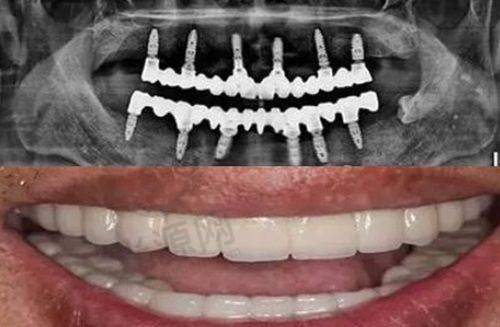

门诊部占地面积达1000平方米,是集口腔种植、口腔矫正、口腔美容、口腔修复、儿童口腔、口腔综合治疗为一体的综合性口腔医院,还有牙周等特色项目。它全周营业,营业时间为星期一至星期天,这为患者提供了极大的便利,无论何时有口腔问题,都能及时前来就诊。

门诊部拥有一支专精的医生团队,其中胡继芬医生是口腔执业医师,从业时间长达30年,曾是丽江市永胜县口腔科主事医师,也是口腔全科医师。她从事临床口腔治疗工作30余年,对固定修复和微痛治疗有丰富的实践经验。还有杨国强医生,他是执业医师,从业经验15年,熟悉口腔科各种常见病,能对各种类型的牙髓病、根尖周病、牙周病作出明确诊断。这样的医生团队为患者的口腔健康提供了有力的保护。